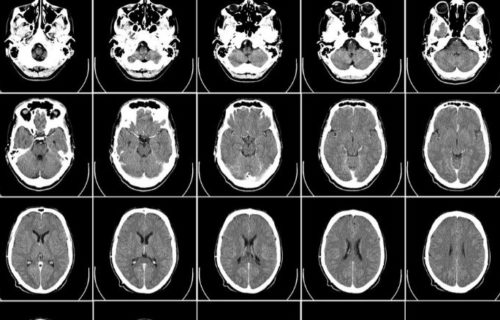

Anti-oxidants in the brain and Alzheimer’s

Alzheimer’s is a progressive neurodegenerative disorder that causes cognitive decline and memory loss. By peeping into the brains of various